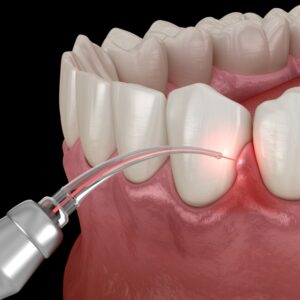

스케일링은 치아 표면과 잇몸 사이에 쌓인

단단한 치석과 세균 막을 제거하는 치료입니다.